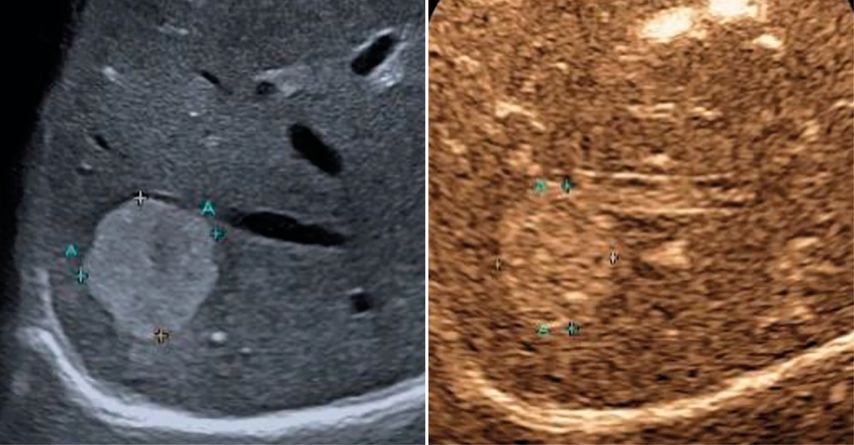

In der früharteriellen Phase zeigen benigne Läsionen wie Hämangiome typische Füllungsmuster ohne „wash-out“ in der Portal- oder Spätphase (Abb.1). Maligne Läsionen hingegen weisen meist ein rasches „wash-out“ auf und stellen sich in der Spätphase hypokontrastiert dar (Abb.2).3,4

Abb. 1: Typisches Kontrastmittelverhalten eines Hämangioms in der Spätphase mit Hyperenhancement gegenüber dem umgebenden Leberparenchym (rechts)

Abb. 2: Darstellung einer hochgradig Metastasen-suspekten Raumforderung bei Mamma-Neoplasie im linken Leberlappen im B-Bild-Modus (rechts) sowie in der Spätphase nach Gabe von 1,6 ml SonoVue® mit Darstellung eines deutlichen „Wash-out“-Phänomens in der Spätphase 4 Minuten nach Injektion des Kontrastmittels (links)